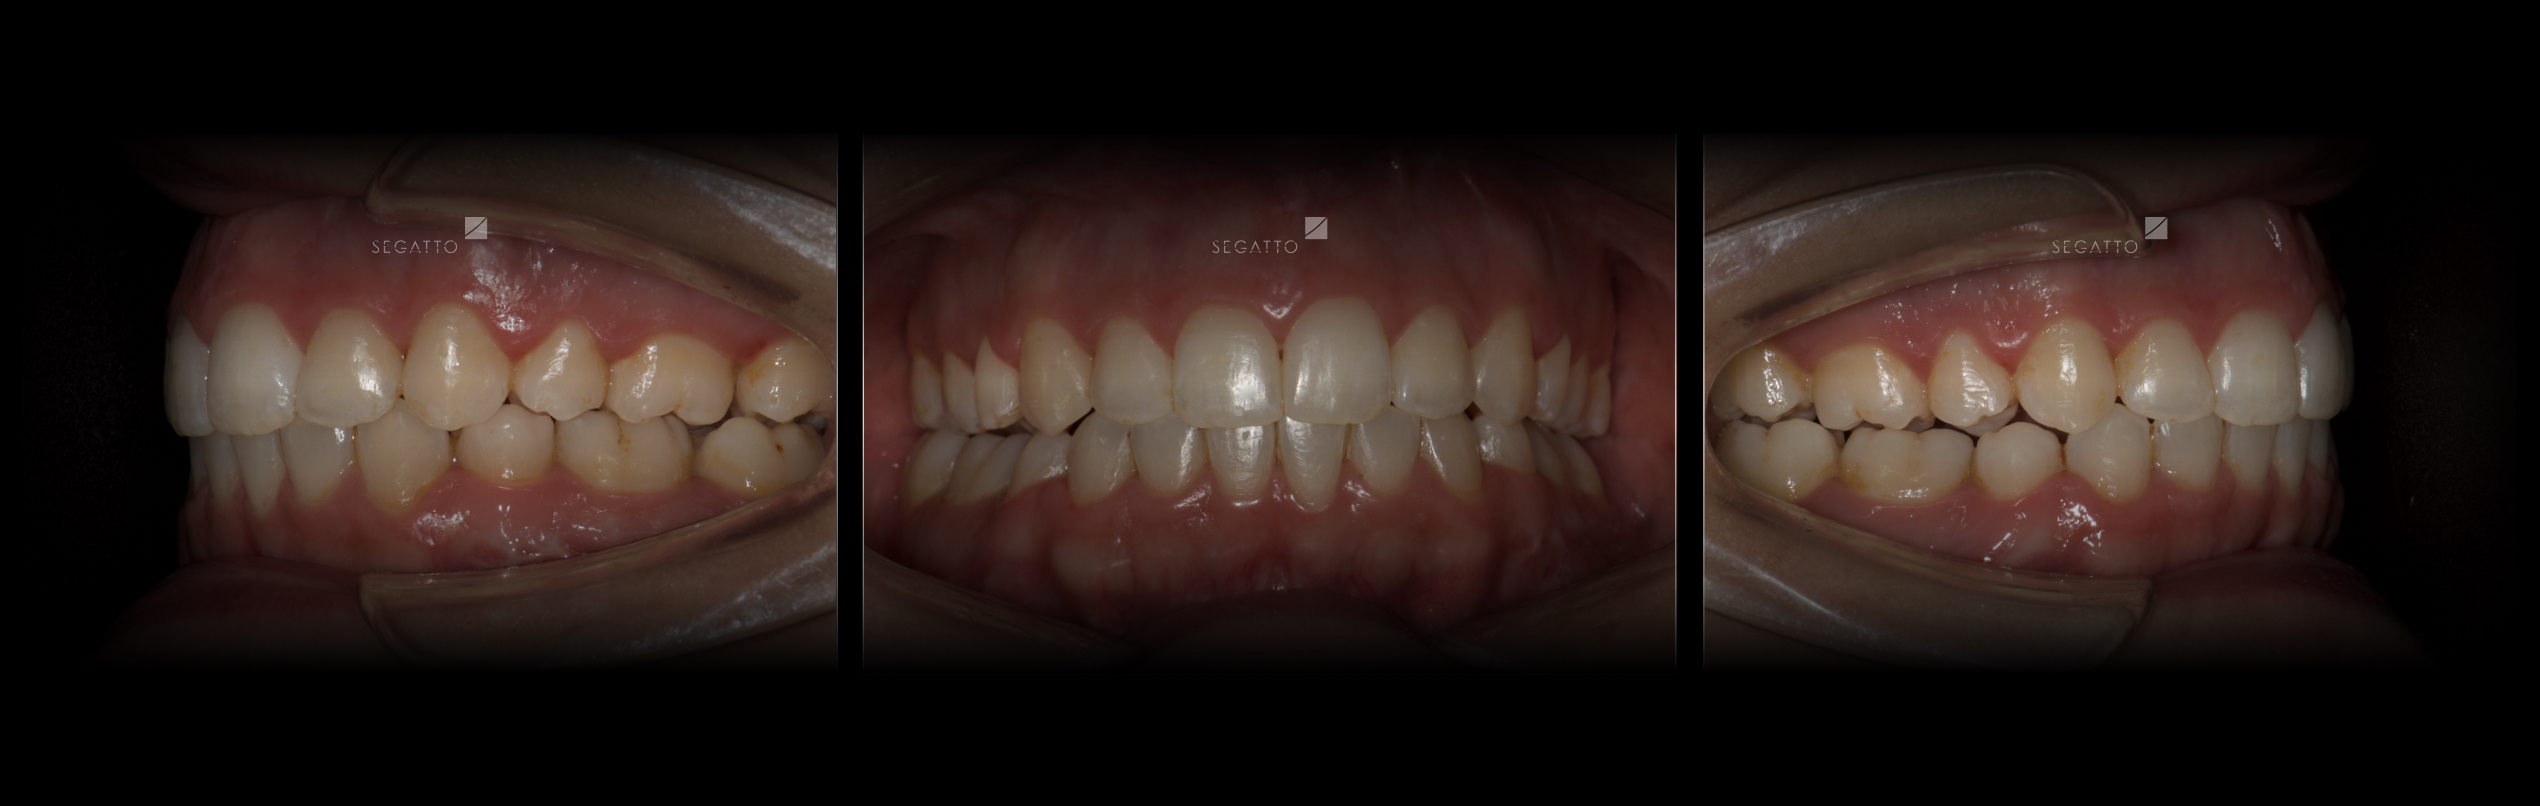

Orthodontics

Cases